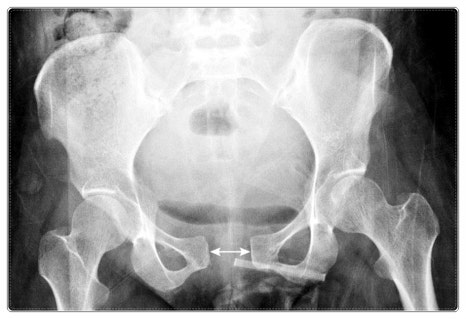

그런데 만약 골반이 틀어져 한쪽 다리 길이에 차이가 생긴다면 어떻게 될까요?

보행 자체가 비대칭이 되고, 균형을 맞추기 위해 한쪽 팔이 더 크게 움직이게 됩니다.

이런 패턴이 오랜 시간 반복되면 어깨는 점점 더 많은 부담을 떠안게 되고,

결국 힘줄에 과부하가 쌓이면서 손상이 진행될 수 있습니다.